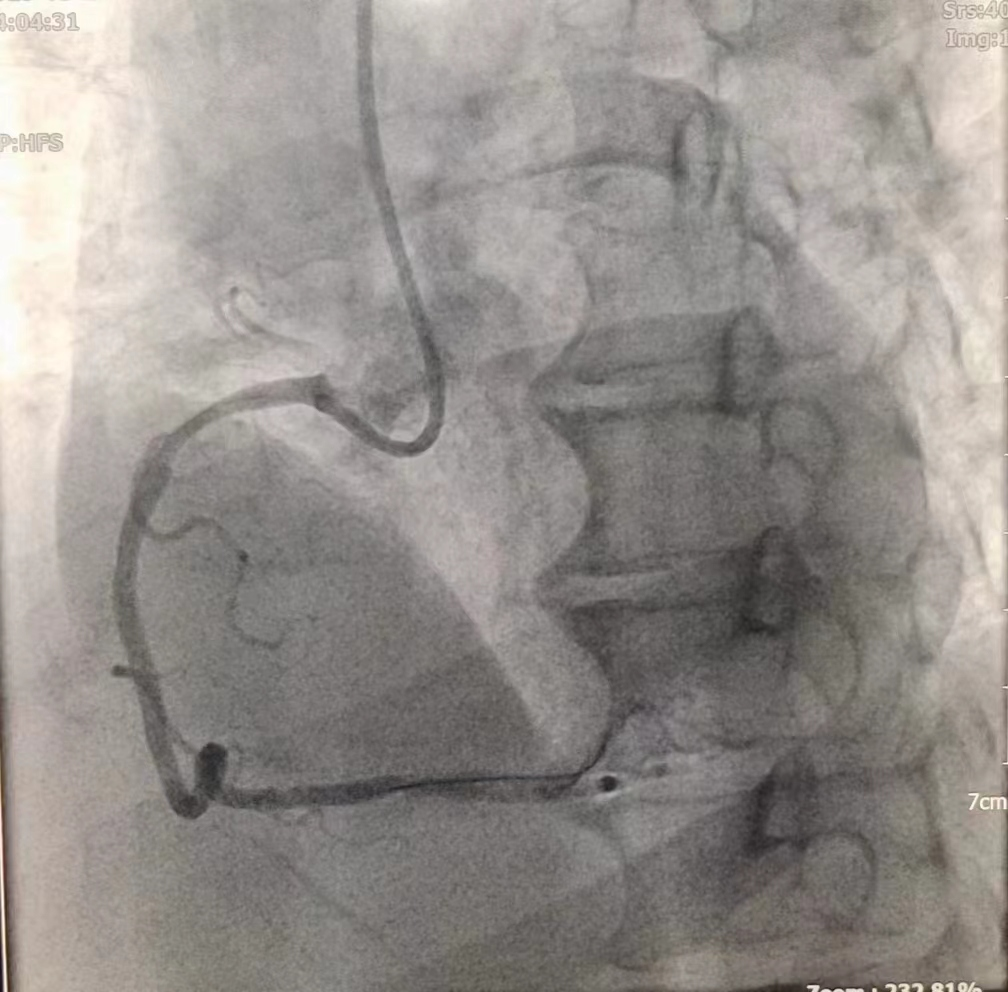

女性患者,49歲,突發暈厥急診我院,經診斷為:冠狀動脈粥樣硬化性心臟病、2型糖尿病。導入造影導管行冠狀動脈造影示:冠狀動脈分布呈左冠優勢型,LM未見明顯狹窄,血流TIMI3級;LAD全程多發斑塊,中段狹窄約60%,遠端狹窄約50%,D1未見明顯狹窄,血流TIMI3級;LCX未見明顯狹窄,血流TIMI3級,RCA近端狹窄約50%,中段發出圓錐支后完全閉塞,血流TIMI0級,急診開通血管并充分擴張,殘余狹窄仍然嚴重。在與患者及家屬溝通時,其了解得知臨床有一種新型的可吸收支架,植入體內后支架能完全被降解和吸收,希望能用這種新型的支架進行手術治療。由于生物可吸收支架有著嚴格的適應癥,因此經過嚴格篩選評估,最終對患者進行了Xinsorb生物可吸收支架置入術。支架植入術前經過充分預擴張,按照規范的可吸收支架操作流程,快速送入可吸收支架到病變部位,精準定位后14個大氣壓釋放,生物可吸收支架后擴球囊擴張。充分球囊后擴張,以保證支架貼壁良好,血流速度正常,造影完美,手術順利結束。

(圖為右冠病變術前影像)

(圖為生物可吸收支架置入術后影像)